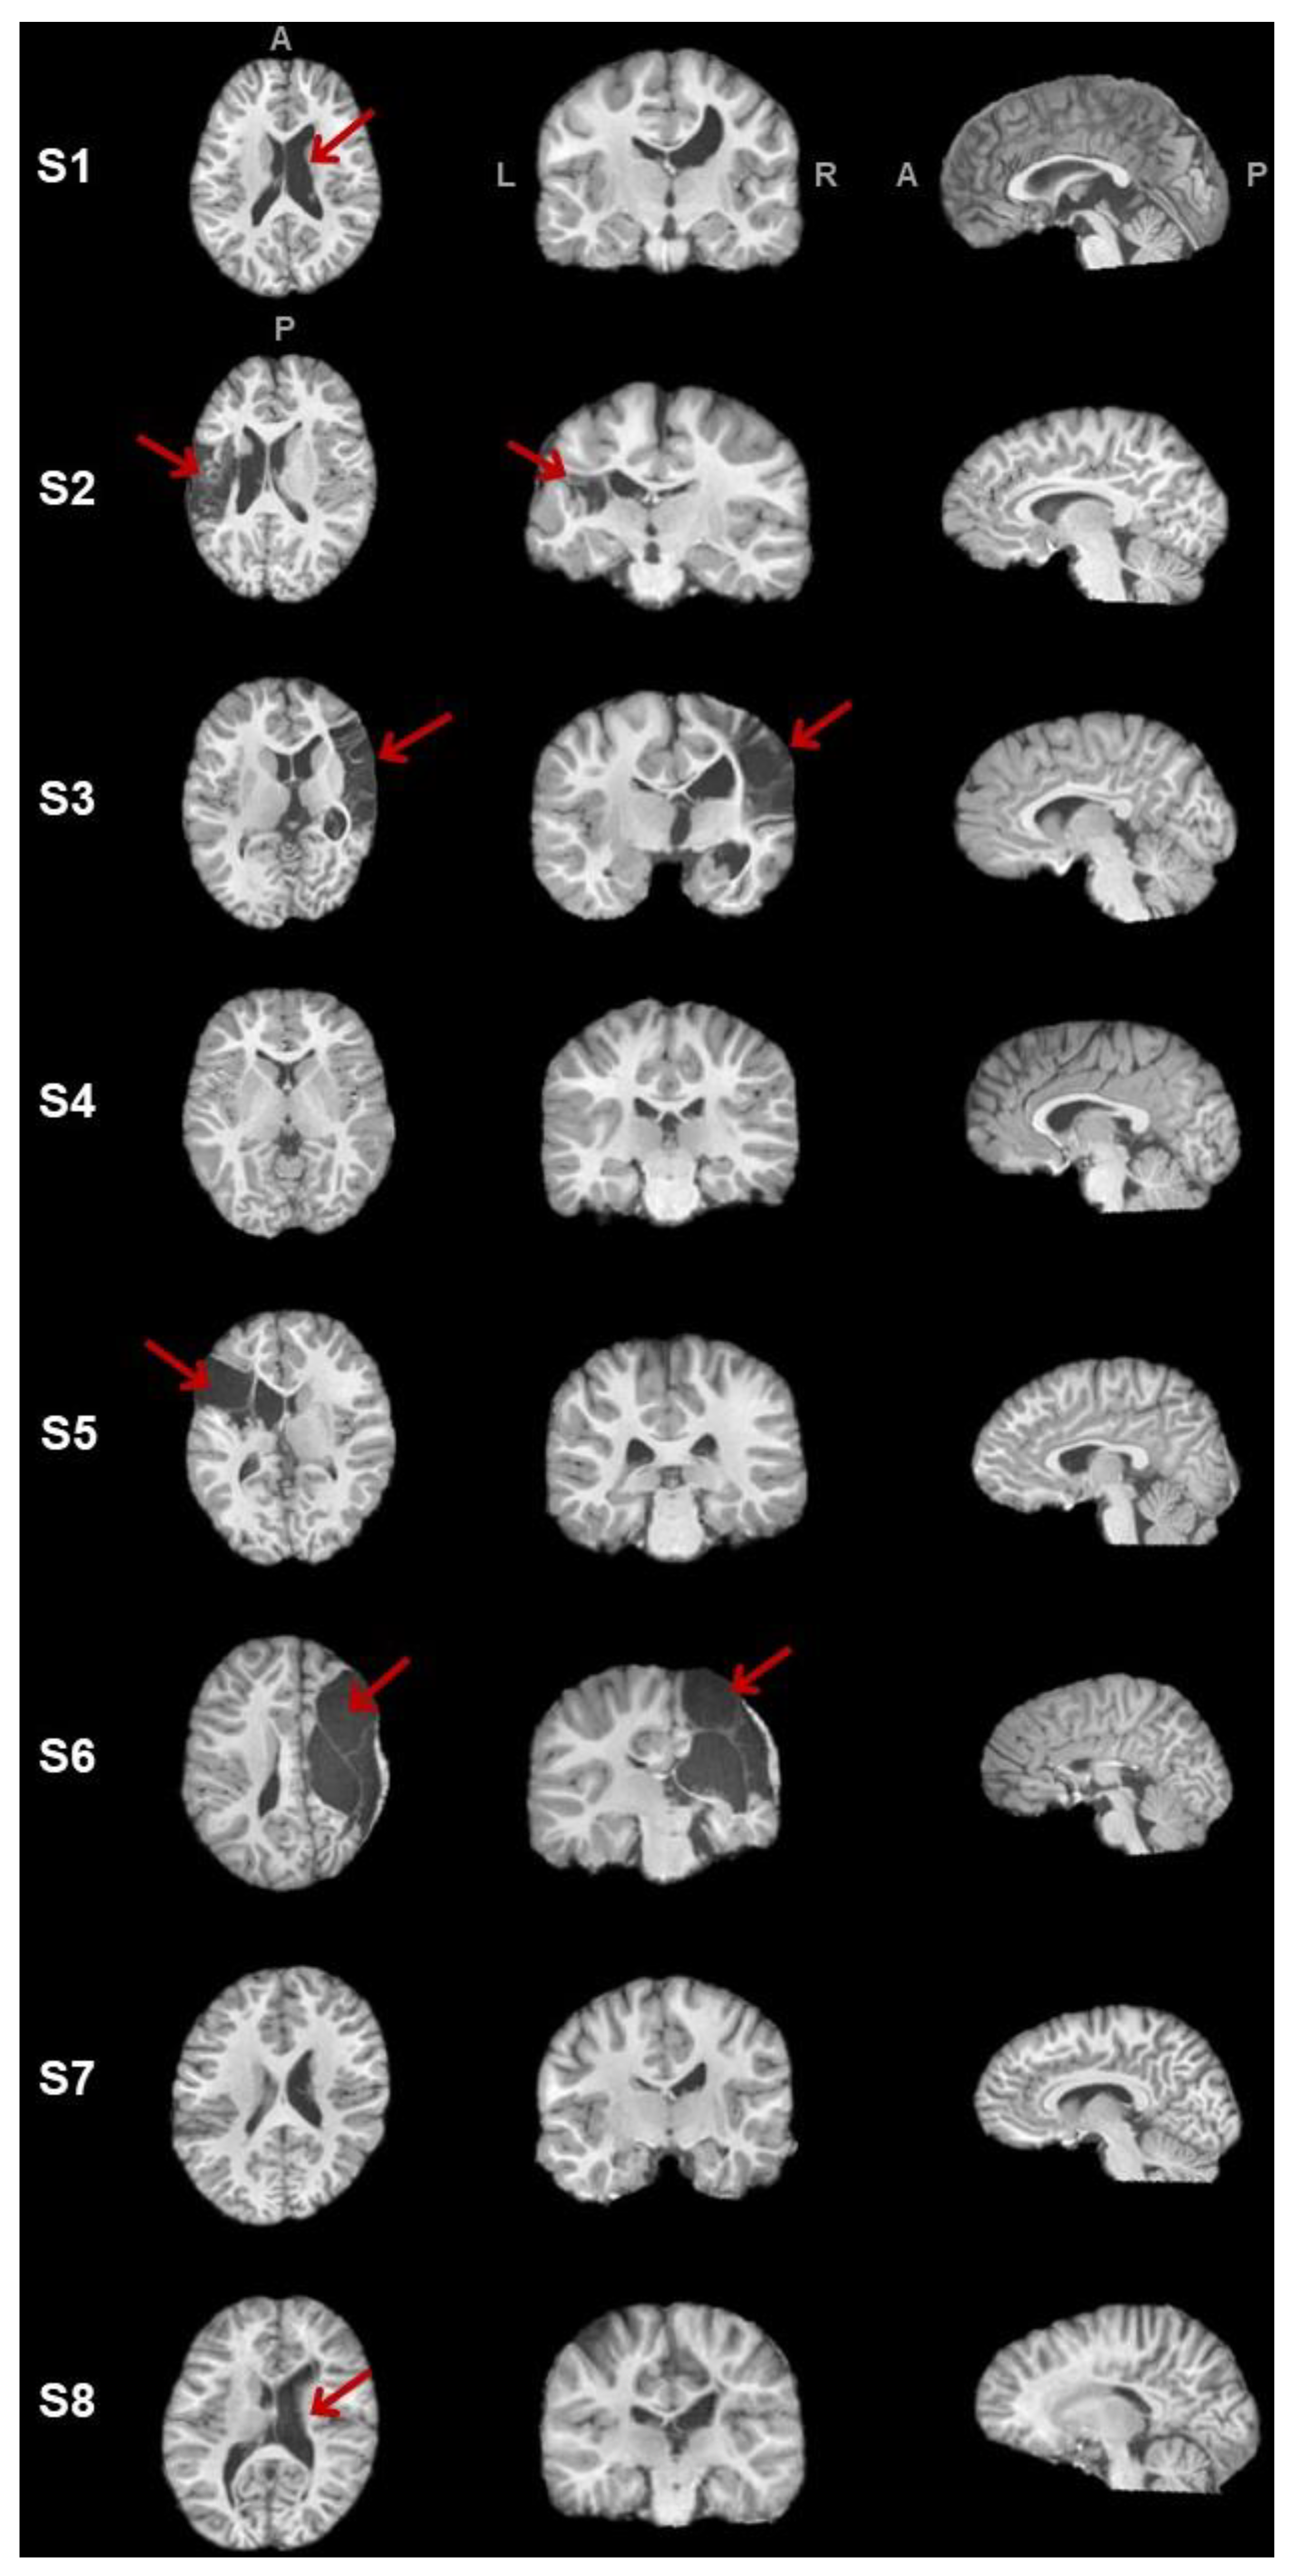

3.1. Clinical Data

3.2.1. Corticospinal Tracts

3.2.2. Corpus Callosum